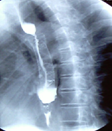

Gastrografin swallow - Colonojejunal anastomosis following esophagogastrectomy for extensive esophageal and gastric burns (Courtesy Dr. V. Penopoulos)